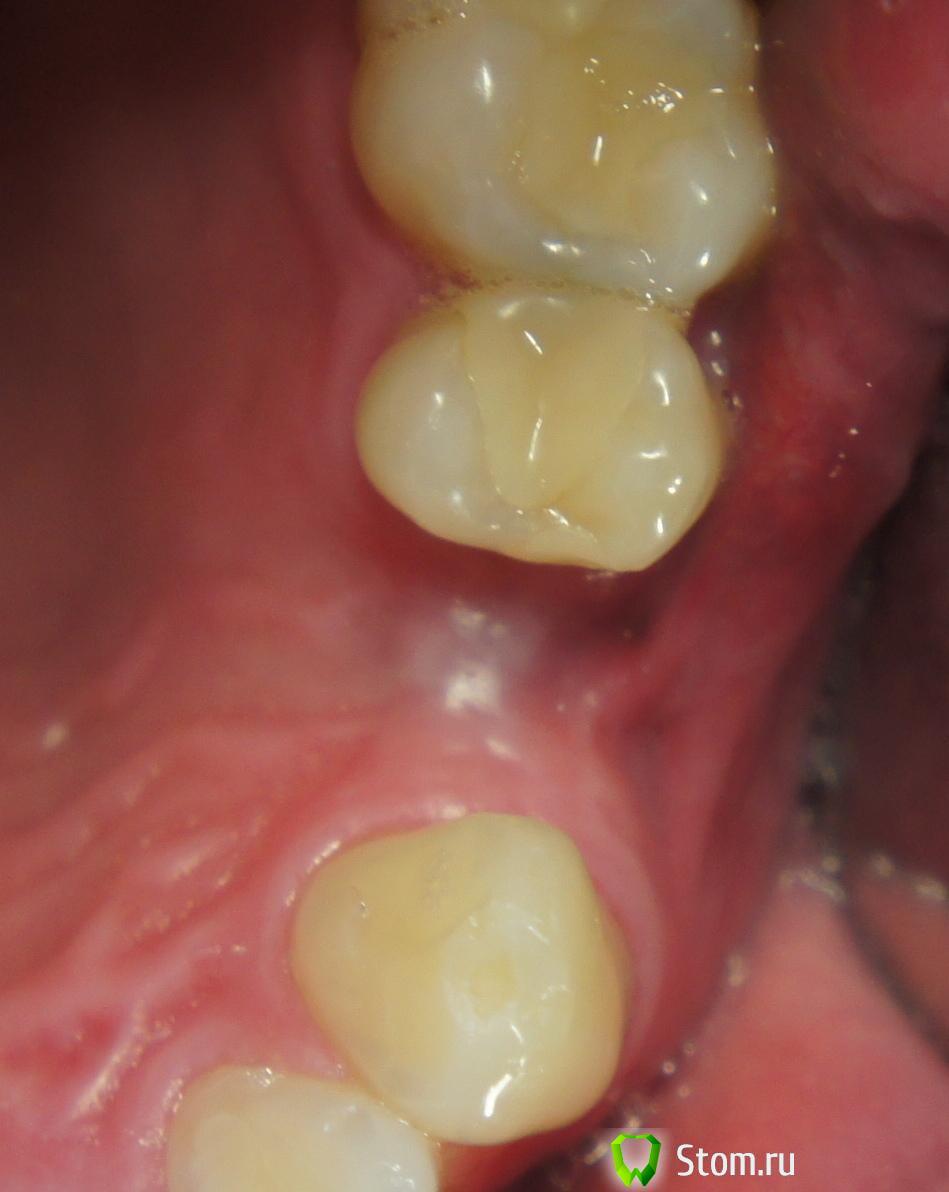

Ст@ся Опубликовано 15 апреля, 2012 Поделиться Опубликовано 15 апреля, 2012 Опять же, чисто моя ИМХа: тут нужно было или на ножке лоскут выворачивать комбинированный, либо стт тоннелем укладывать.Например, вот так:(но тут я предварительно перед имплантацией сдт сажала полгода назад)http://s019.radikal.ru/i620/1204/aa/163c8ffbda46.jpg 1 Ссылка на комментарий